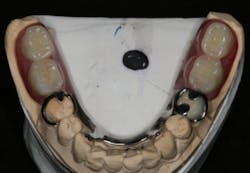

In this case, the diagnostic wax-up of the mounted models gave the technician the new position of the upper incisal edge. The technician then set the maxillary teeth appropriately using models and additional photographs. At the same time, tooth No. 20 was restored, but the lab technician kept the crown and lower partial to predictably create the lower occlusal plane and easily articulate this with the upper immediate denture (figure 18). Note the improved curve of Spee in Figures 19 and 20. Upon completion of the prosthesis, treatment was completed as outlined and the results made the patient feel very comfortable functionally, esthetically, and phonetically.

Figure 18